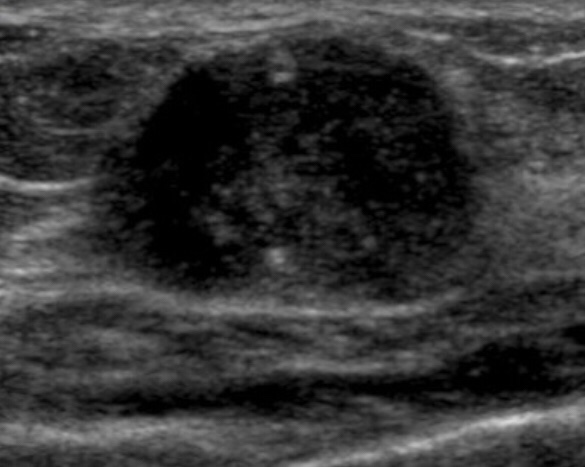

It’s been several months since I found out there were rogue cells in my boob. At that time the doctor and I decided we would wait 6 months or so, then take another look to see exactly how those cells were changing.

Tomorrow is MRI day. I’m pretty sure I won’t piss myself.